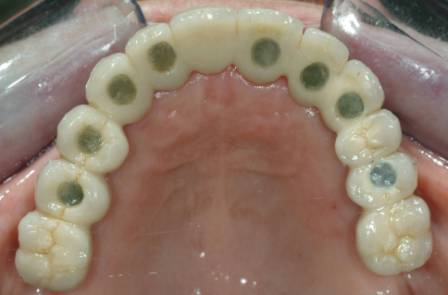

Riabilitazione superiore Implantoprotesi